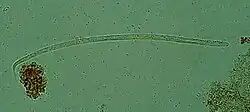

Onchocerca volvulus, the causative agent of river blindness | |

Onchocerca volvulus is a filarial (arthropod-borne) nematode (roundworm) that causes onchocerciasis (river blindness), and is the second-leading cause of blindness due to infection worldwide after trachoma. It is one of the 20 neglected tropical diseases listed by the World Health Organization, with elimination from certain countries expected by 2025.[2]

Onchocerca volvulus parasites obtain nutrients from the human host by ingesting blood or by diffusion through their cuticle. They may be able to trigger blood-vessel formation because dense vascular networks are often found surrounding the worms.[6] They are distinguished from other human-infecting filarial nematodes by the presence of deep transverse striations.[7]

It is a dioecious species, containing distinct males and females, which form nodules under the skin in humans. Mature female worms permanently reside in these fibrous nodules, while male worms are free to move around the subcutaneous tissue. The males are smaller than females, with male worms measuring 23 mm in length compared to 230–700 mm in females.[7]

The release of oocytes (eggs) in female worms does not depend upon the presence of a male worm, although they may attract male worms using unidentified pheromones.[8] The first larval stage, microfilariae, are 300 μm in length and unsheathed, meaning that when they mature into microfilariae, they exit from the envelope of the egg.[9]